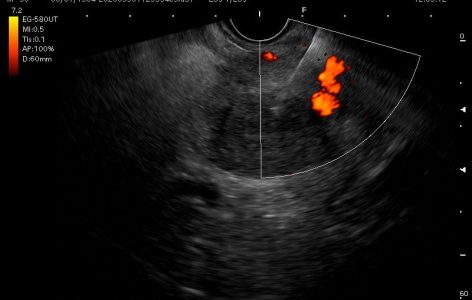

Για το λόγο αυτό τα τελευταία χρόνια χρησιμοποιούνται σχεδόν αποκλειστικά τα linear ηχοενδοσκόπια. Μέσω ειδικού επεξεργαστή αναπαράγονται υπερηχοτομογραφικές εικόνες ενώ μέσω του συστήματος  Doppler είναι δυνατή η ανίχνευση της ροής του αίματος και συνεπώς ο εντοπισμός αγγειακών δομών με αποτέλεσμα να είναι δυνατή η ασφαλής στόχευση για παρακέντηση όγκων ή κυστικών αλλοιώσεων.

Εξάλλου, με τη χρήση ειδικών λογισμικών είναι δυνατή η διενέργεια ελαστογραφίας καθώς και υπερήχου με χρήση σκιαστικών ουσιών με σκοπό την πληρέστερη απεικόνιση των σημείων ενδιαφέροντος. Οι  λεπτές βελόνες που χρησιμοποιούνται για τη λήψη κυτταρολογικού ή ιστολογικού υλικού, προσαρμόζονται στο ενδοσκόπιο και μέσω ειδικού καναλιού που διαθέτει το ενδοσκόπιο προωθούνται στο σημείο ενδιαφέροντος.